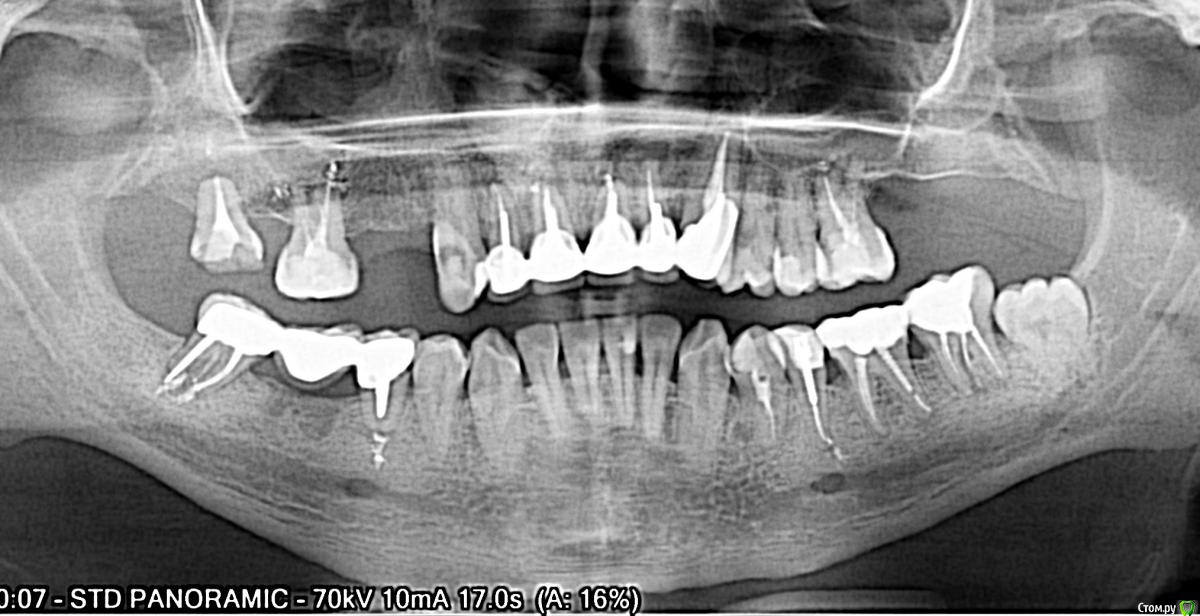

Илья1986 Опубликовано 3 апреля, 2018 Поделиться Опубликовано 3 апреля, 2018 Здравствуйте, подскажите как правильно поступить и подобрать план лечения, а так же хорошего врача. С раннего возраста начались проблемы с зубами, удалили множество нервов из зубов в школьном возрасте,потом зубы стали быстро разрушаться, ставил коронки на разрушенные зубы, их хватало на год или на два.4 года назад откололся передний зуб, в клинике поставили 5 коронок на передние верхние зубы. Перед установкой коронок перелечивал. 2 года назад стали болеть зубы когда простываю, сделал КТ и обнаружились кисты. Мне 31 год и я продолжаю терять зубы с большей скоростью. В мае 2017 года поставили коронки с 45-47, но неделю назад пришлось удалить 45, тк. половина корня рассосалась. Врач одномоментно вкрутил 45,46, но 45 не прижился. Помогите обрести веру в себя и в современную стоматологию, заранее спасибоснимки прилагаю. Ссылка на 3Д снимок https://yadi.sk/d/LVKZiOWR3Tdc39 Ссылка на комментарий

Илья1986 Опубликовано 12 апреля, 2018 Автор Поделиться Опубликовано 12 апреля, 2018 Все же какие рекомендации будут? Все верхние удалить, если склонны к кистообразованию или оставить? нужна ли подсадка кости и синуслифтинг? Ссылка на комментарий

Irouil Опубликовано 12 апреля, 2018 Поделиться Опубликовано 12 апреля, 2018 Нет зубов, склонных к кистообразованию. Лучше всего сделайте скриншоты с КТ, качать всю томограмму навряд кто стане Синус лифты с очень большой долей вероятности потребуются Ссылка на комментарий

Bier Опубликовано 12 апреля, 2018 Поделиться Опубликовано 12 апреля, 2018 с большой долей вероятности зубы придется удалить. Ссылка на комментарий

Илья1986 Опубликовано 18 апреля, 2018 Автор Поделиться Опубликовано 18 апреля, 2018 Еще очень интересует вопрос - делать одномоментную или двухэтапную имплантацию передних зубов? Десна при улыбке не видна. Врач предлагает установку 2х имплантов вместо 4х передних зубов. Будет ли в этом случае уходить десна и кость в тех местах, где нет имплантов? Ссылка на комментарий

Bier Опубликовано 19 апреля, 2018 Поделиться Опубликовано 19 апреля, 2018 правильное решение 2 вместо 4х зубов. Если есть возможность - ставьте одномоментно. Ссылка на комментарий